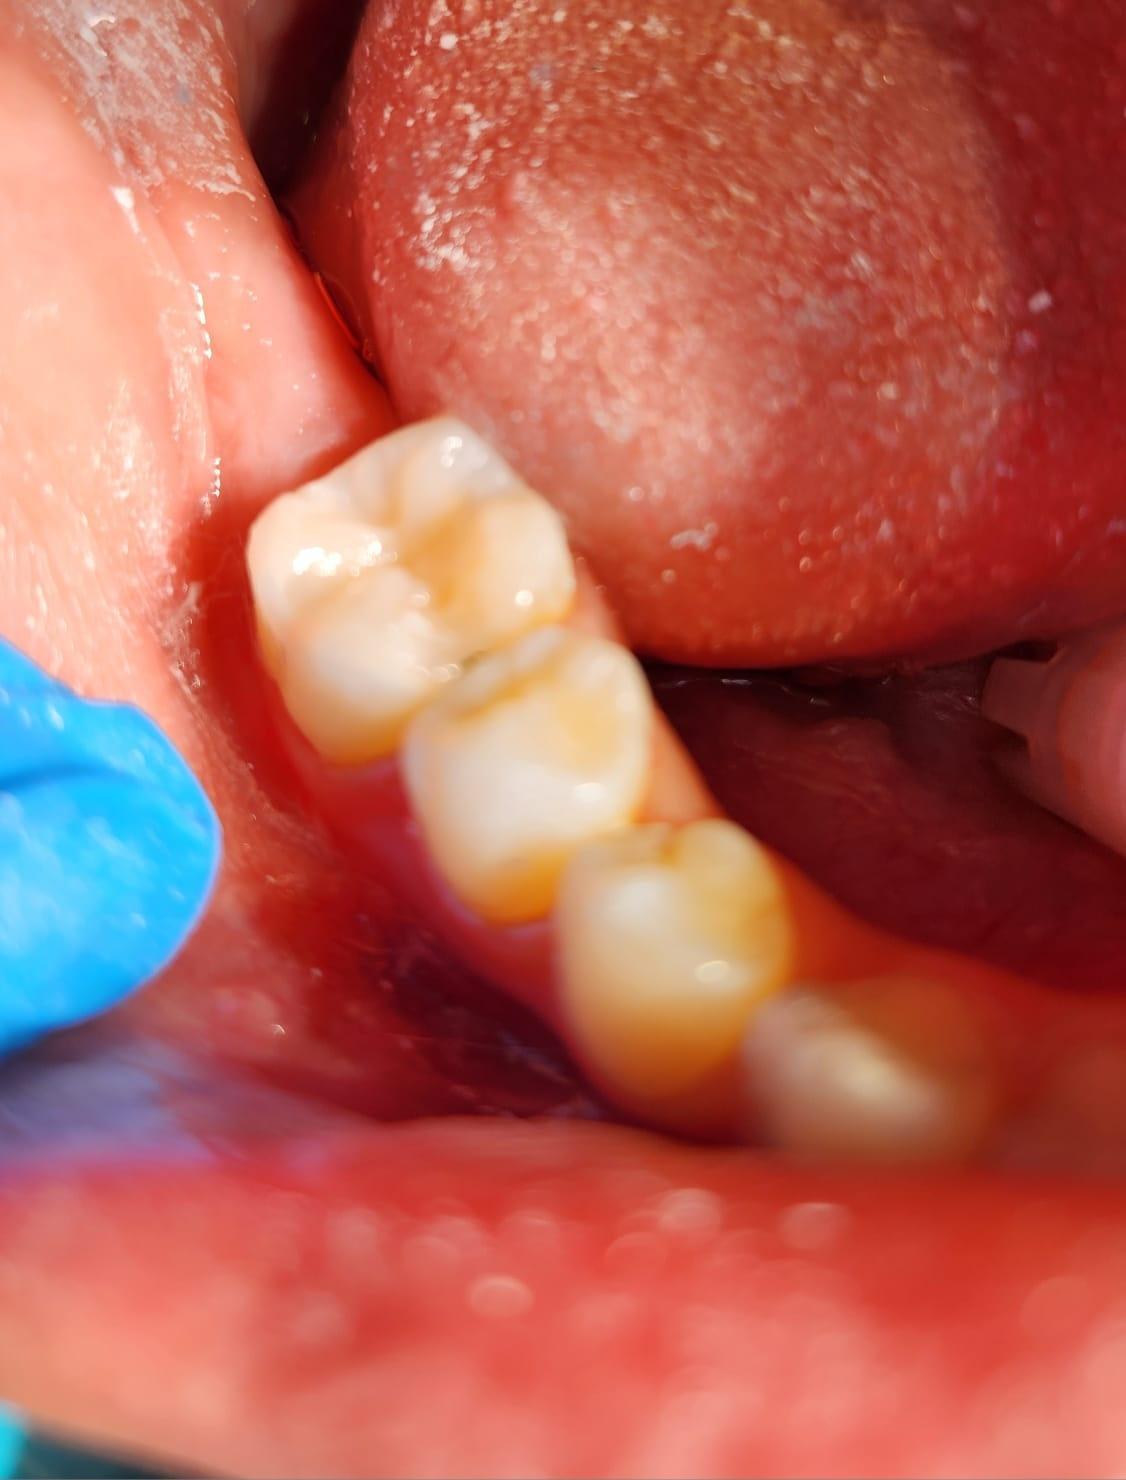

Clinica LUY ESTHETIC ART defineste parodontoza ca fiind rezultatul direct al placii dentare, care se depune pe suprafata dintilor, dar si in apropiere de marginea gingivala. Aceasta boala duce la pierderea dintilor, chiar daca ei sunt aparent sanatosi si nu prezinta carii. Edentatiile, afecteaza vorbirea, aspectul, dar si capacitatea de a mesteca.

Boala parodontala are un caracter progresiv. Pentru cazurile mai grave, recomandam tratamentul parodontal chirurgical rezectiv sau regenerativ.

O igiena bucala necorespunzatoare, fumatul, placa bacteriana si alte boli generale, permit bacteriilor sa se dezvolte in cavitatea bucala.

Semnele aparitiei paradontozei:

– gingiile sangereaza la periaj;

– gingii rosii si inflamate;

– mobilitatea sau deplasarea dintilor;

– retractii gingivale cu expunerea radacinilor dentare;

– halena.